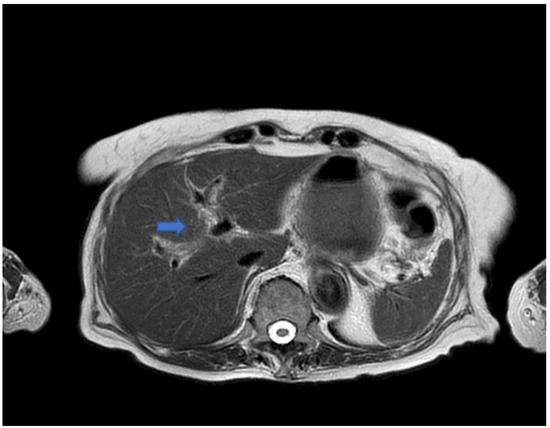

2. Case Presentation and Results